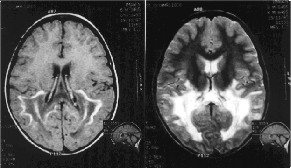

Esta enfermedad se caracteriza por la presencia de una degeneración progresiva de la corteza suprarrenalY MOTORA, lo que da lugar a una insuficiencia suprarrenal o Enfermedad de Addison, asociada a la desmielinización de la sustancia blanca del sistema nervioso central (sistema formado por el encéfalo y la médula espinal), con pérdida de la cubierta de mielina (vaina de sustancia blanca que recubre los nervios) de un tipo de fibras nerviosas del cerebro.